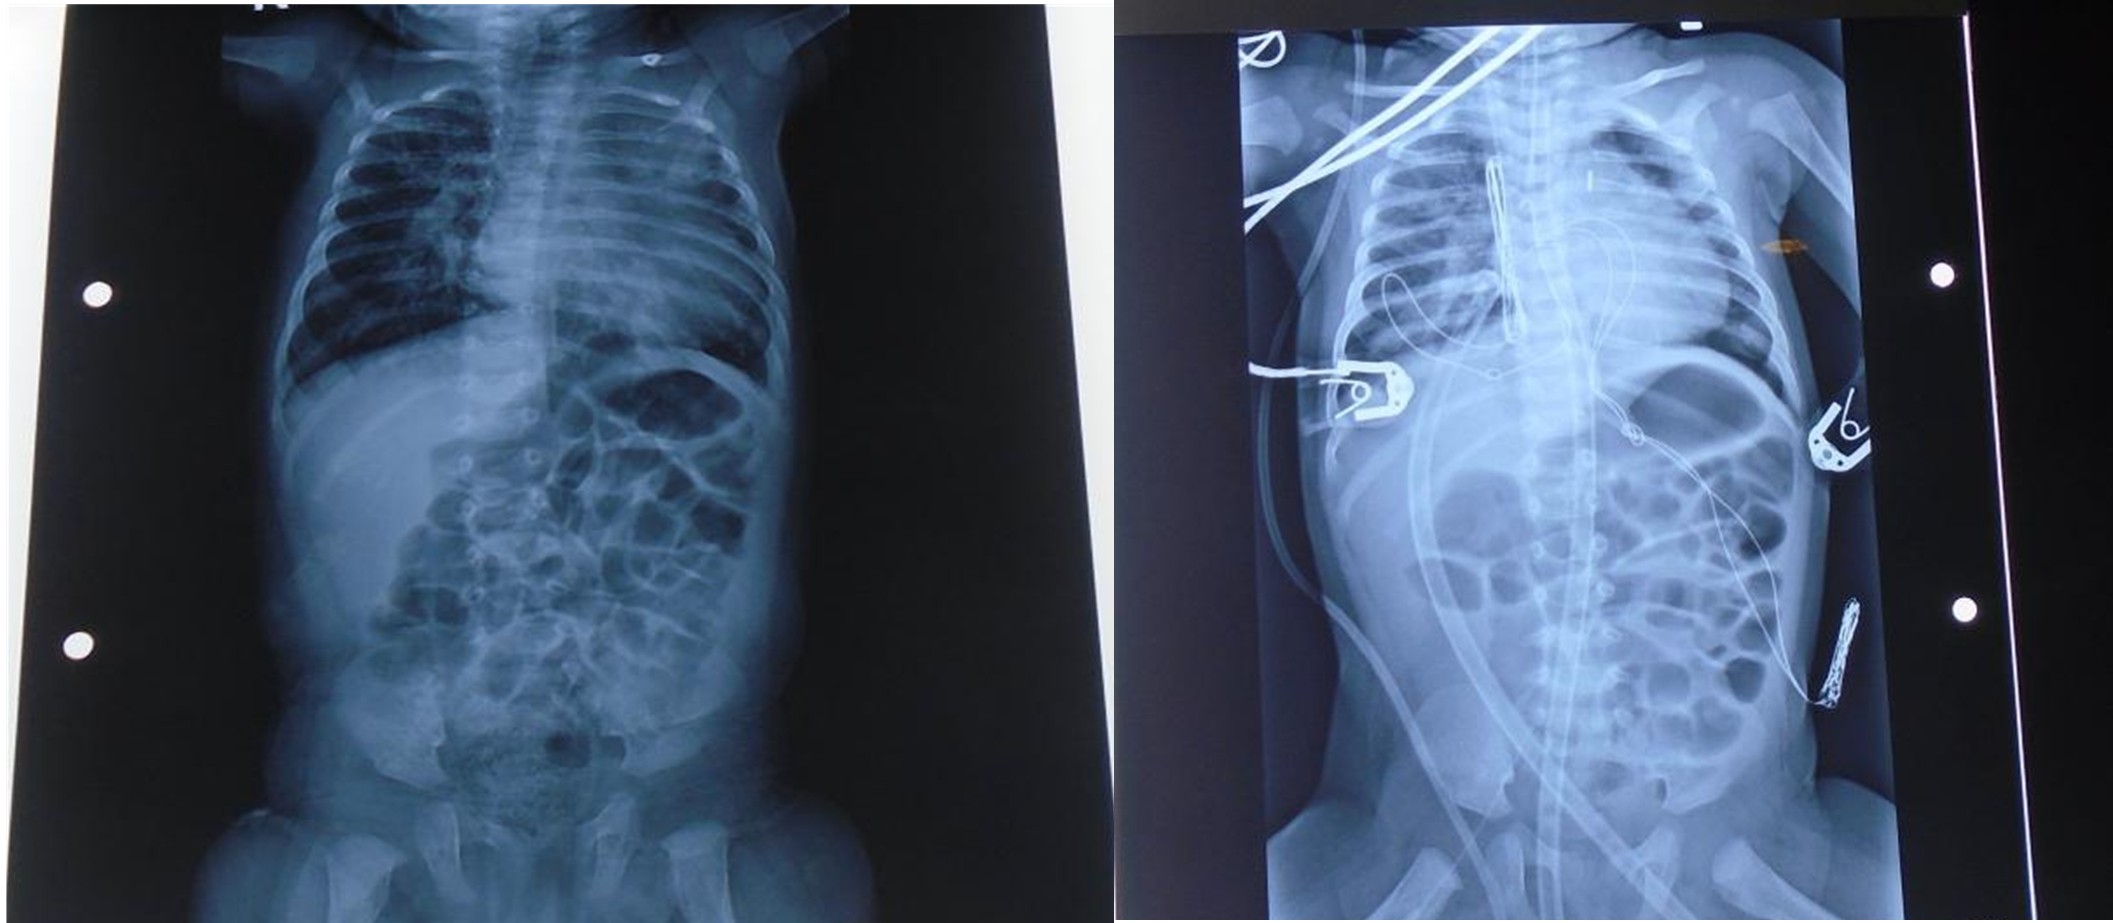

Pre OP ECG

X-Ray

ECHO Report

Impression

- A cyanotic congenital heart disease: large peri membranous VSD with muscular extension left to right shunt

- Good Biventricular function

- Increased QP: QS (>2:1)